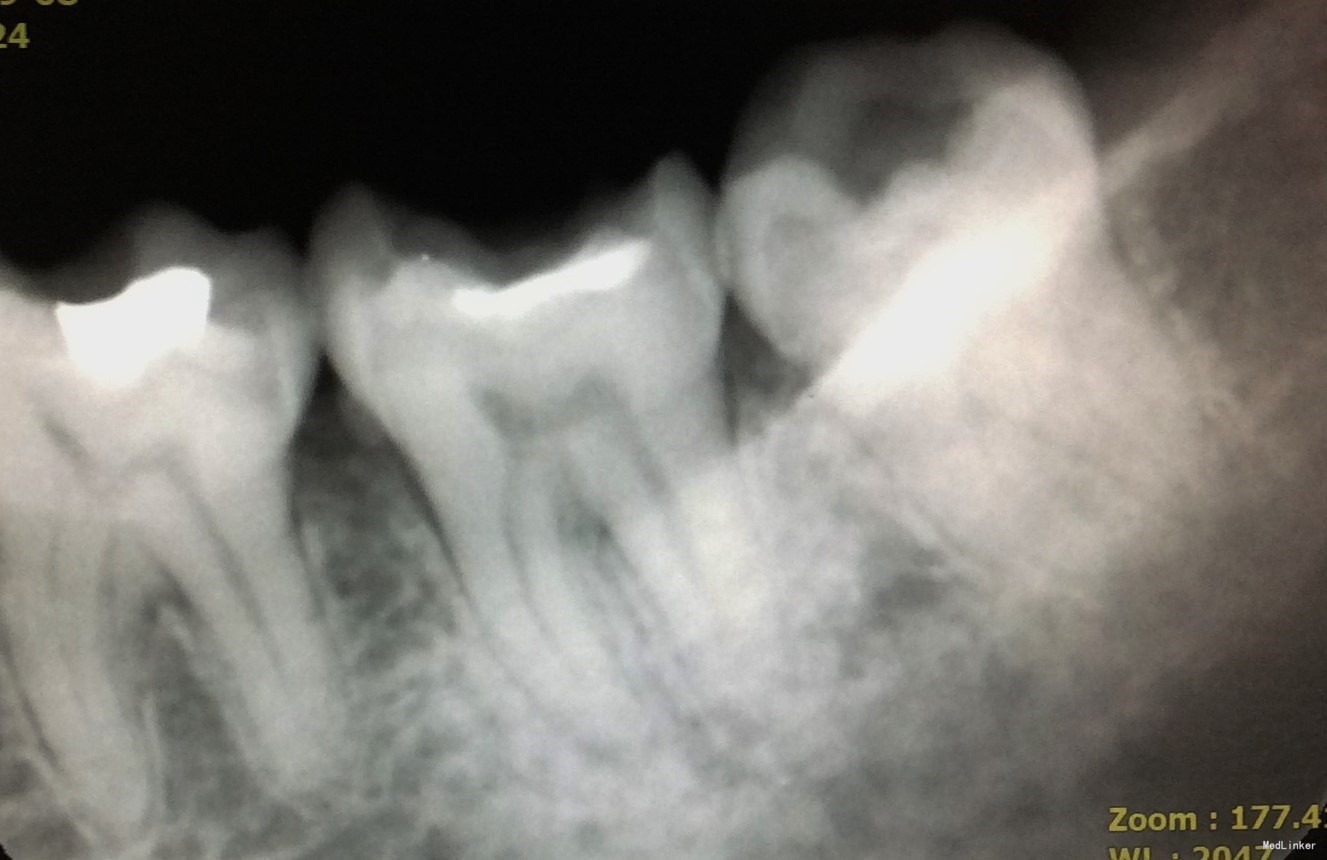

检查:46牙合面见大面积树脂充填物,部分树脂材料脱落,远中可探及继发龋,深,可探及穿髓孔,冷刺激迟钝,热刺激迟钝,电活力测试58,探(+),叩(-);牙龈及牙槽粘膜未见窦道,根尖区扪诊无不适。

X线检查:牙体组织见大面积高密度影,远中影像密度减低,累及髓腔;根尖周未见低密度影;远中牙槽嵴顶高度降低。